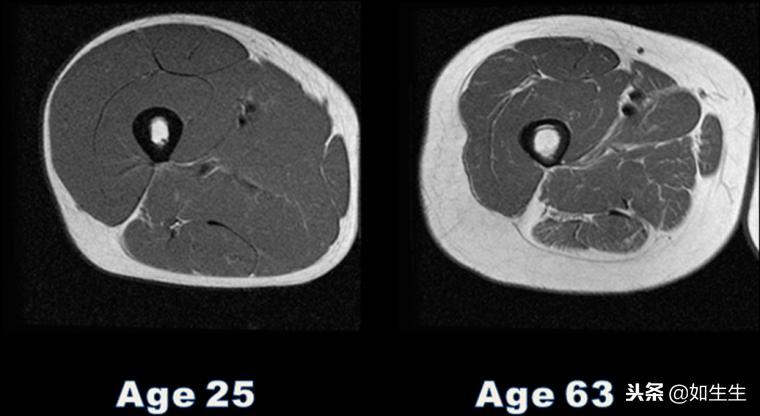

科学家对比了两个年龄分别为25岁和63岁的、具有相同体重指数(BMI值,目前国际上常用的衡量人体胖瘦程度的一个标准)的测试者的肌肉含量,发现因为年龄的不同,两个人的肌肉量和脂肪量的比例完全不同,其中,63岁测试者的肌肉量远少于25岁的,取而代之的是较高的脂肪量。(如下图:左边的是25岁测试者的X光照片,右边的是63岁测试者的,图片中颜色偏白的那一圈,既外面那一圈是脂肪,而里面偏暗的那一圈是肌肉)

测试者肌肉量对比